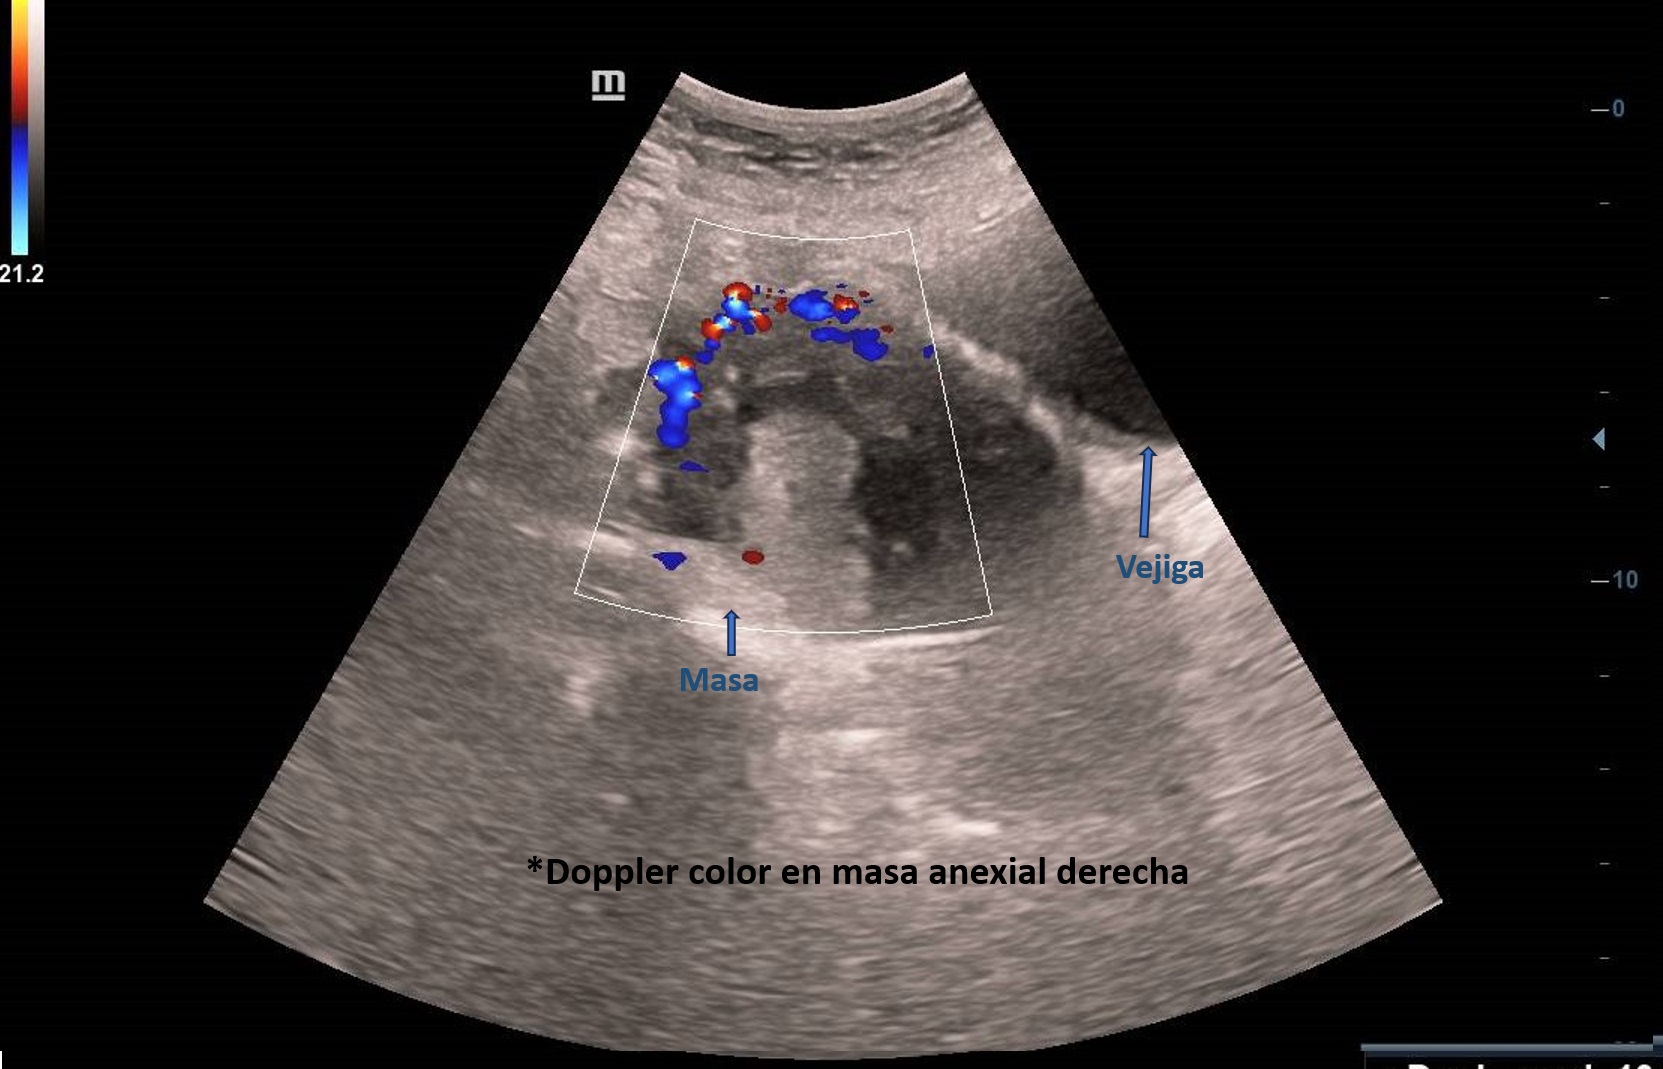

Ecografía abdominal en Atención Primaria: masa derecha adyacente a vejiga, vascularizada, de ecogenicidad heterogénea de unos 6 cm sin quedar clara dependencia del ovario derecho con imagen hipoecogénica en pelvis sugerente de ascitis. Se deriva paciente a ginecología preferente donde se realiza ecografía transvaginal: Tumoración anexial derecha, contorno irregular sugerente de neoplasia.

El EO se puede clasificar como benigno o maligno dependiendo de las características histológicas. En la ecografía aparece como una masa sólida heterogénea. No existen características ecográficas distintivas exclusivas. Ocasionalmente hay ascitis.